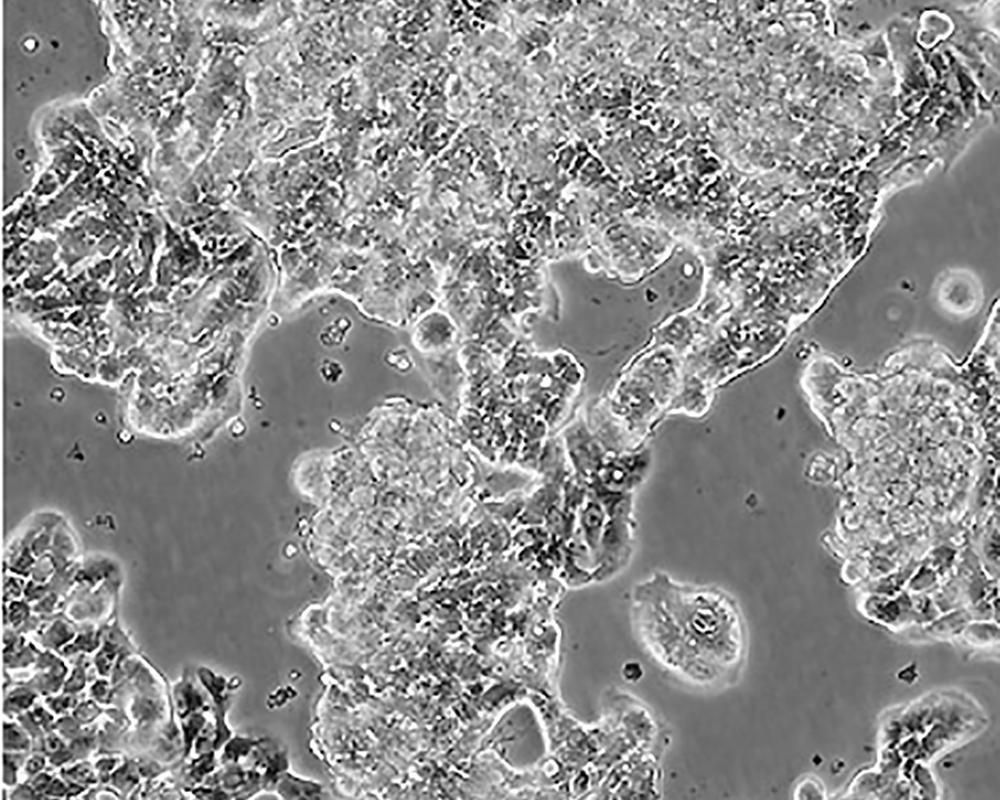

ZR-75-1 [ZR751]

產品名稱 ZR-75-1 [ZR751]

中文名稱 人乳腺癌細胞

組織來源 浸潤性導管癌;腹水轉移;女性

生長特性 adherent

形態特征 epithelial

細胞描述 該細胞產生高水平的黏液素MUC-1 mRNA,低水平的MUC-2 mRNA,但不表達MUC-3基因;表達雌激素受體。